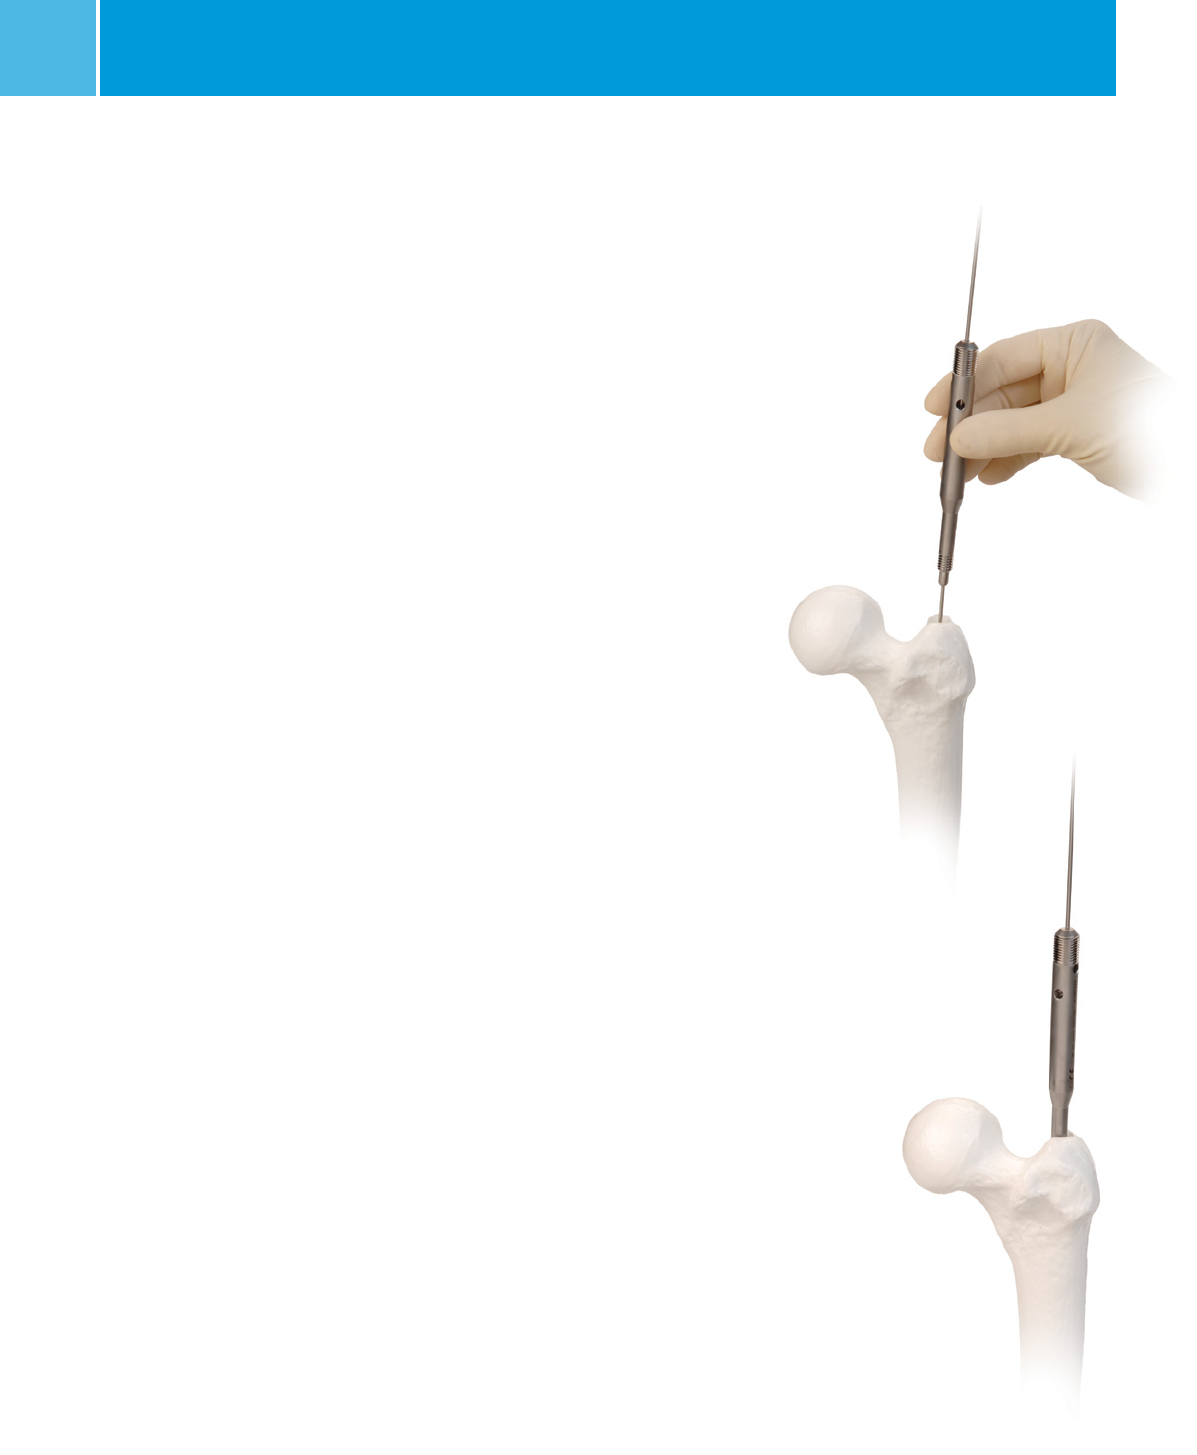

Greater Trochanter Entry Point Nail Insertion

Insert the nail over the guide wire with the arm of the guide

facing anterior to the patient (Figure 16GT). The guide will turn

90° as it passes down the femoral canal. The combination of

the nail’s anatomic shape as well as the flutes in the nail will

help the nail rotate as it passes down the canal. Monitor the

progression of the nail using the C-arm, especially as the nail

is passing through or near the fracture site.

Piriformis Fossa Entry Point Nail Insertion

Fig. 16GT Fig. 16PF

Insert the nail over the guide wire with

the arm of the

guide facing lateral to the patient (Figure

16PF). Monitor

the progression of the nail down the

canal using the

C-arm, especially as the nail is passing

through or near

the fracture site.

If the nail does not pass down the canal

easily, attach the IMPACTION HEAD to

the TARGETING GUIDE HANDLE. Using the

MALLET, impact gently on the IMPACTION

HEAD (Figure 17). Do not strike the guide.

CAUTION: Do not strike excessively as

damage to the targeting guide and bone

may result.

Verify that the CONNECTING BOLT is tight

while impacting. Do not impact on any

other portion of the TARGETING GUIDE

HANDLE or MODULE as this may break

the guide or cause it to lose its accuracy.

If the nail will not advance with

impaction, remove the nail and ream the

canal to a larger diameter at additional

0.5 mm increments or consider using a

smaller diameter nail. Place the top of

the nail in line with or below the surface

of the entry point, depending on its

position relative to the expected screw

location.